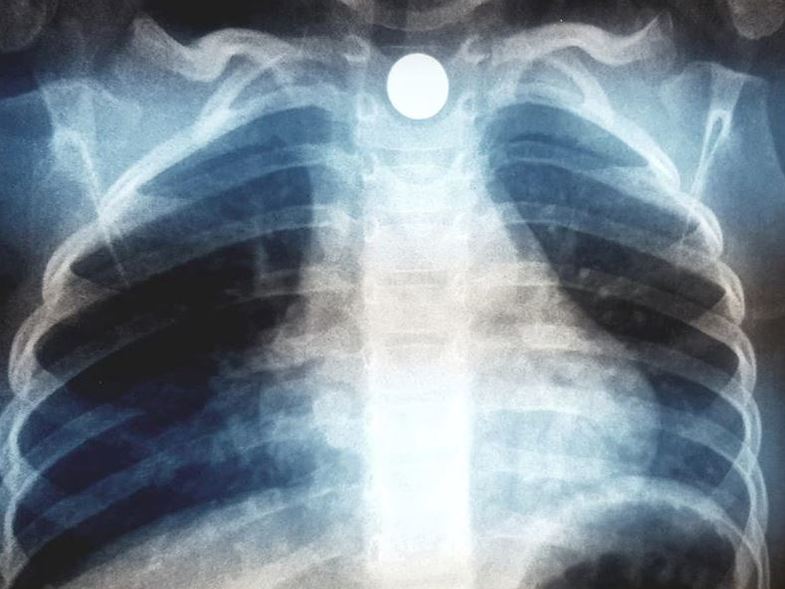

Άγιο είχε ένα παιδί μόλις 2,5 ετών στον Βόλο, που κατάπιε μαγνητάκι ψυγείου και κινδύνευσε με πνιγμό. Στην ακτινογραφία που ανήρτησε ο γιατρός της οικογένειας, διακρίνεται το μαγνητάκι που σφήνωσε στον οισοφάγο του παιδιού.